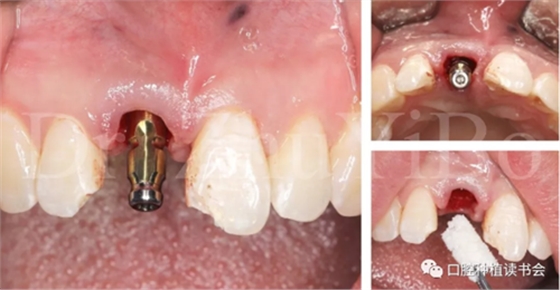

4.2.4取模,制作臨時修復體(圖13)。

圖13 一定要在植骨前,進行取模,有多種方法可以選擇

4.2.5 雙區(qū)植骨,戴牙(圖14,圖15)。

圖14 雙區(qū)植骨需要植到齦緣水平

圖15術后即刻CBCT示:種植體軸向及深度良好

圖16 即刻修復后,患者恢復了美觀